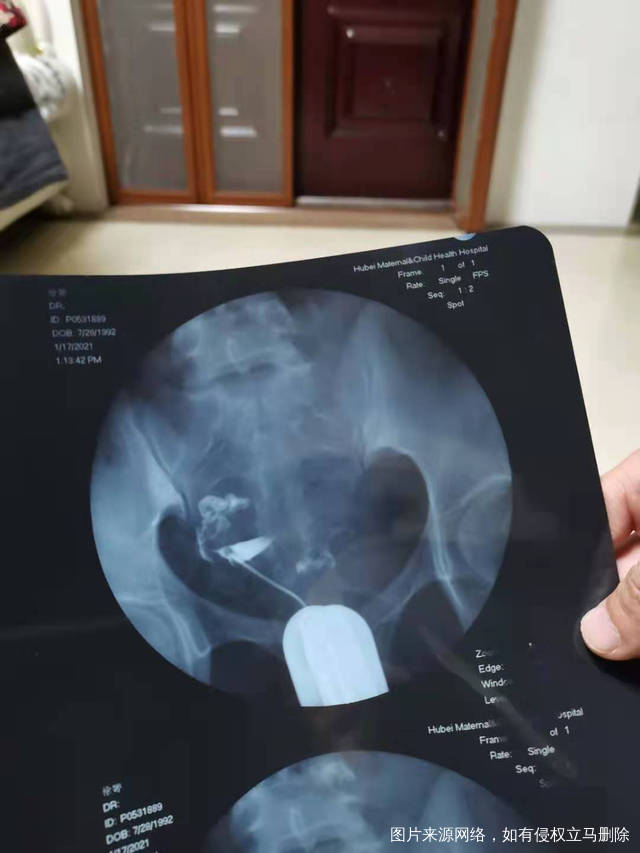

今天做的输卵管造影接下来如何治疗男方精子质量

今天做的输卵管造影,接下来如何治疗?男方精子质量不佳。